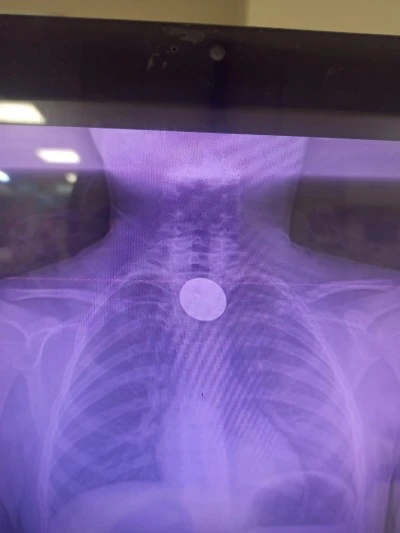

Siirt 1 gün önce Siirt’te İki Uzman Hekim Göreve Başladı Siirt 2 gün önce Siirt Valisi Kızılkaya Yeni Göreve Başlayan Başhekimi Kabul Etti Siirt 2 gün önce Siirt'te Kuduz Riskli Temas ve Profilaksi Eğitimi Düzenlendi Siirt 3 gün önce Siirt Eğitim ve Araştırma Hastanesi’nde Yeni Başhekim Sahaya İndi Siirt 3 gün önce Siirt’te yeni başhekim göreve başladı Gündem 6 gün önce Batman'da yolu kardan kapanan köydeki tansiyon hastası, ekiplerin yardımıyla hastaneye ulaştırıldı Siirt 6 gün önce Siirt’te Sobanın Devrilmesiyle Yaralanan Çocuk, 6 Saatlik Çalışmanın Ardından Hastaneye Ulaştırıldı Siirt 1 hafta önce Vali Kızılkaya’dan Siirt Eğitim ve Araştırma Hastanesi’ne Ziyaret Siirt 1 hafta önce Siirt'te yolları kardan kapanan köylerdeki hastalar ekiplerce hastanelere ulaştırıldı Siirt 2 hafta önce Siirt’te Balkondan Düşen Yaşlı Kadın Hayatını Kaybetti Siirt 2 hafta önce Siirt Eğitim ve Araştırma Hastanesinde SDS Kapsamında Değerlendirme Yapıldı Siirt 2 hafta önce Siirt’te kulak akıntısı şikayetiyle hastaneye gitti, kafa tabanında kitle çıktı Siirt 2 hafta önce Siirt’te Hastanede Erişilebilirlik Güçlendirildi Gündem 2 hafta önce AK Parti Genel Başkan Yardımcısı Yalçın, Şırnak'ta İl Danışma Meclisi Toplantısı'nda konuştu: Siirt 2 hafta önce Siirt’te Madeni Para Yutan Çocuğun Boğazındaki Para Çıkarıldı Siirt 2 hafta önce Siirt’te Akşam Polikliniğiyle Günde Bin Kişiye Sağlık Hizmeti Siirt 3 hafta önce İl Sağlık Müdürlüğü Yöneticilerinden Siirt Eğitim ve Araştırma Hastanesi’ne Ziyaret Siirt 3 hafta önce Pervari Devlet Hastanesi’nde SDS Denetimi Yapıldı Siirt 3 hafta önce Hacıoğlu’ndan Kurtalan Devlet Hastanesi’ne Ziyaret Siirt 4 hafta önce Siirt Milletvekili Gül’den Hastane Ziyareti Siirt 4 hafta önce Siirt'te yolları kardan kapanan köylerdeki hastalar hastanelere ulaştırıldı